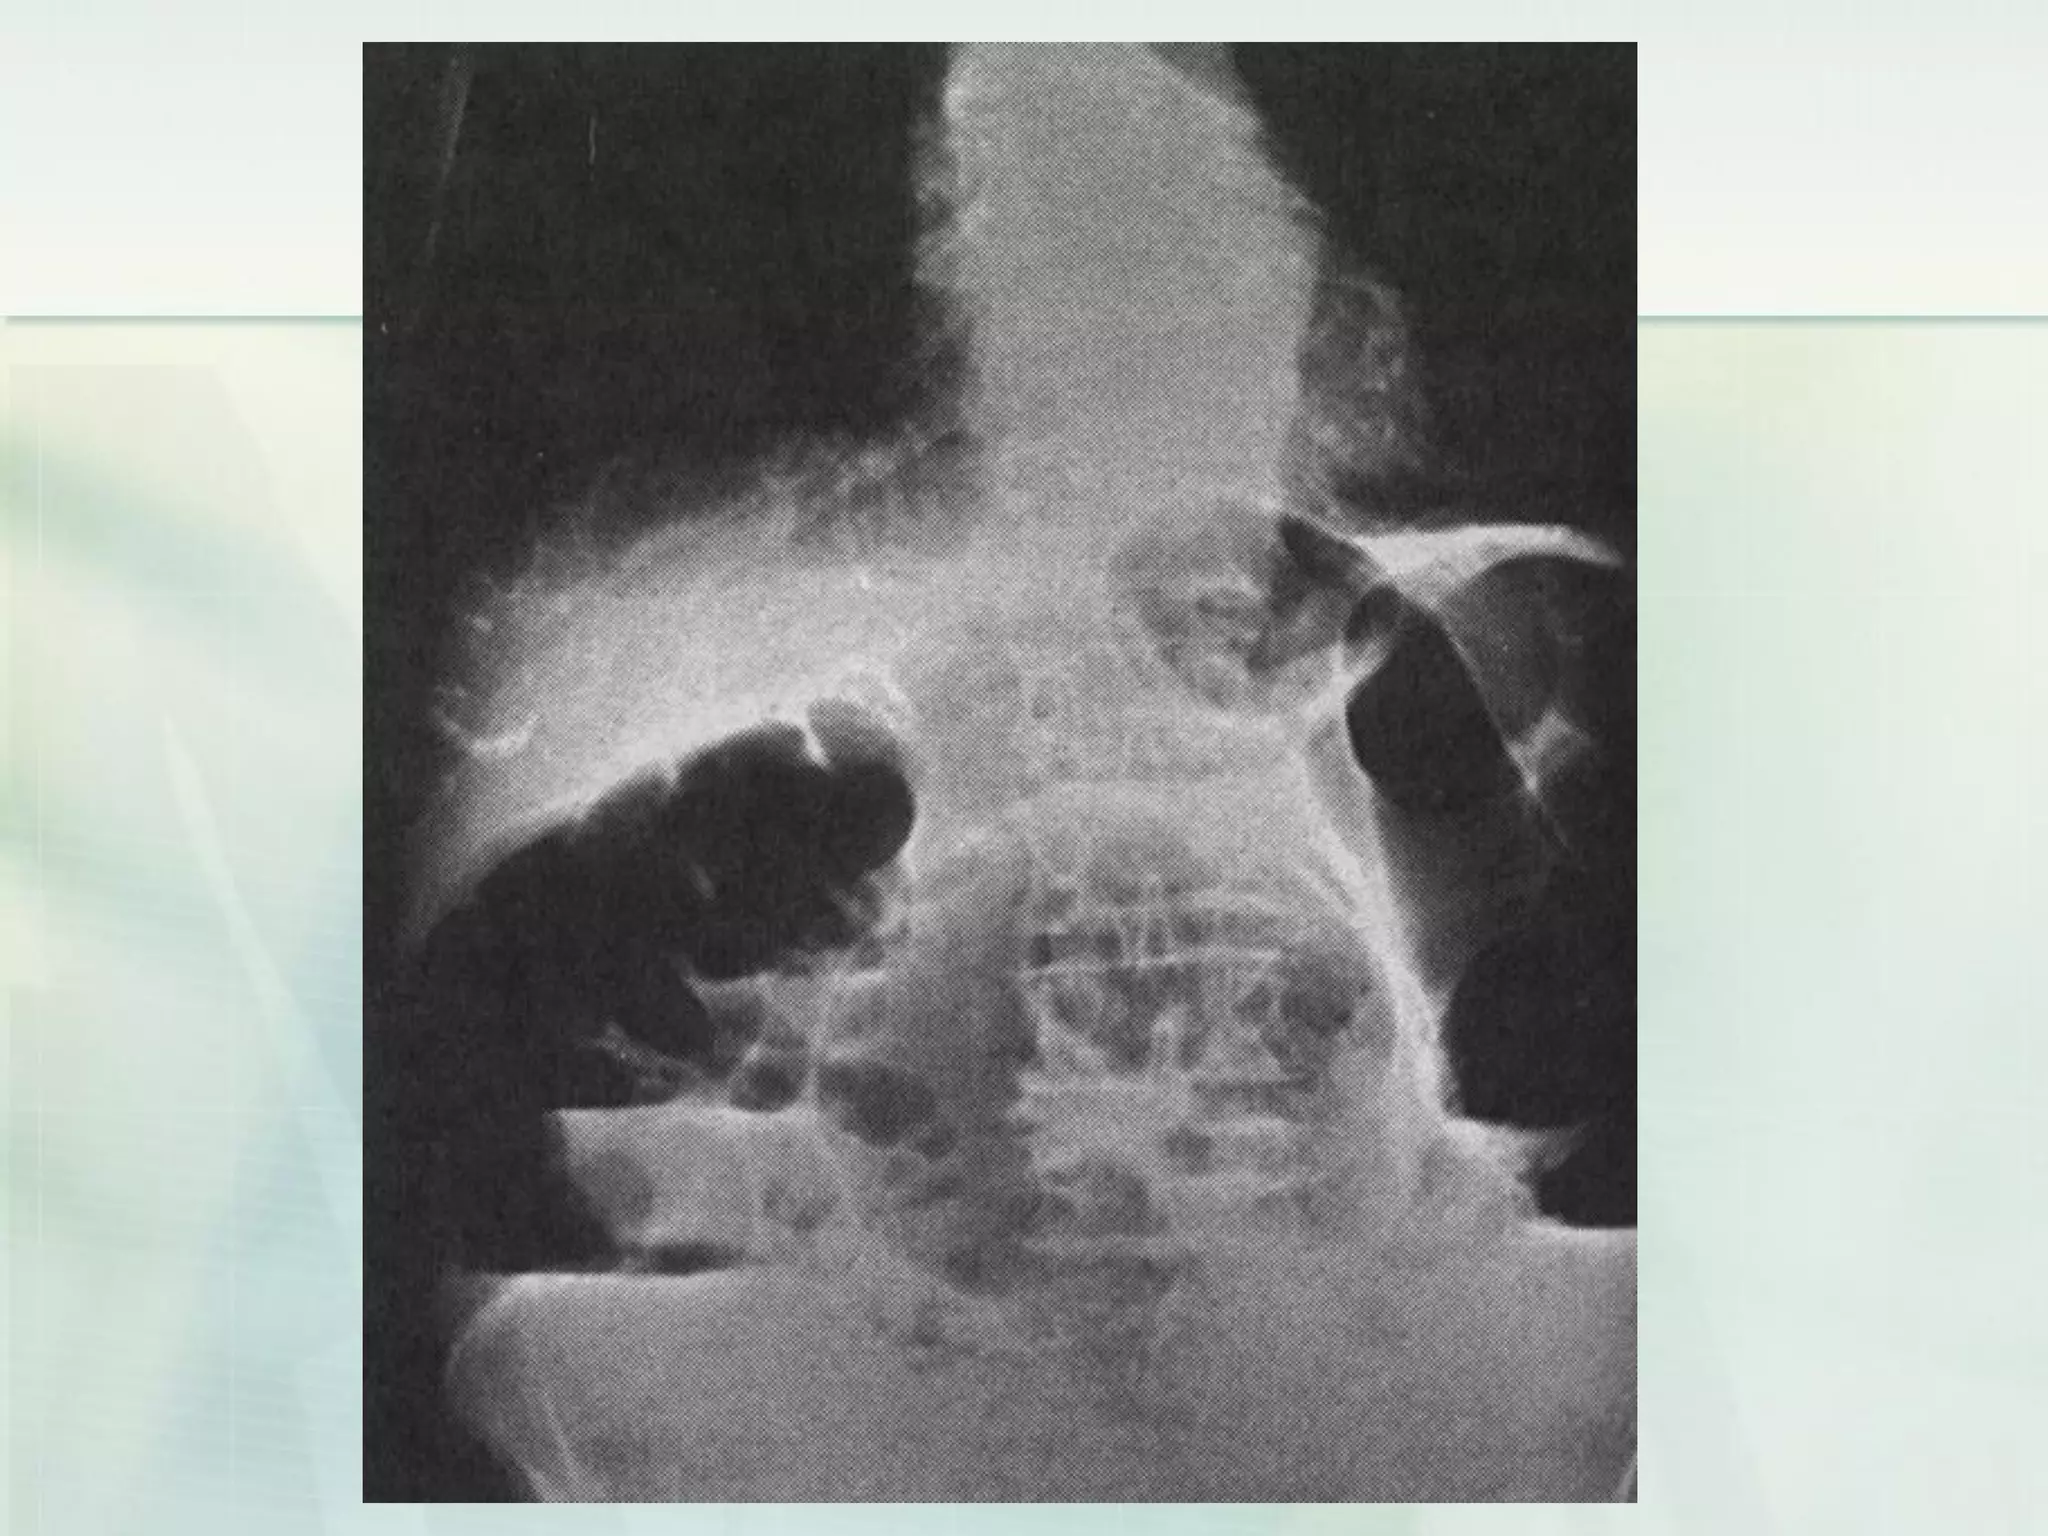

 An abdominal plain film is usually performed in the

 Signs of small bowel obstruction include bowel

dilatation proximal to the site of obstruction, air–fluid

levels, paucity of large bowel gas, bowel wall

thickening, a fixed loop, and ground glass appearance

signifying intraluminal fluid.

 In early small intestinal obstruction, however, there

may still be gas in the large bowel due to incomplete

evacuation of contents distal to the point of obstruction.

 Air–fluid levels may suggest small bowel obstruction in

a patient with a consistent history, though this finding

can be present in any illness which decreases bowel

motility resulting in ileus. Plain films can also appear

normal in the setting of small bowel obstruction.

Laboratory investigations (Small bowelobstruction)  An abdominal plain film is usually performed in the upright position.  Signs of small bowel obstruction include bowel dilatation proximal to the site of obstruction, air–fluid levels, paucity of large bowel gas, bowel wall thickening, a fixed loop, and ground glass appearance signifying intraluminal fluid.  In early small intestinal obstruction, however, there may still be gas in the large bowel due to incomplete evacuation of contents distal to the point of obstruction.  Air–fluid levels may suggest small bowel obstruction in a patient with a consistent history, though this finding can be present in any illness which decreases bowel motility resulting in ileus. Plain films can also appear normal in the setting of small bowel obstruction.